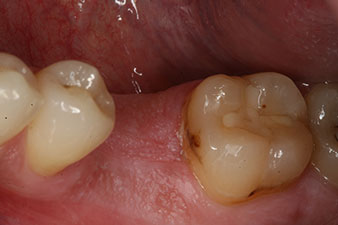

Klinische Ausgangslage

Abb. 1: Klinische Ausgangslage nach Abheilung der Extraktionsalveole 36: Die Knochenbasis ist breit und es ist genügend keratinisierte Gingiva vorhanden.

Bei einem 28-jährigen Patienten mit ausgeprägter Raucheranamnese musste Zahn 36 als Folge einer rezidivierenden apikalen Parodontitis extrahiert werden.

Wegen der weitgehend intakten Nachbarzähne kam als Lückenversorgung nur ein Implantat in Frage.